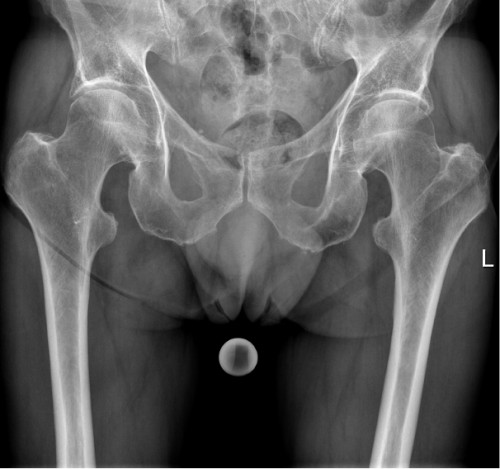

Ein 78-jähriger Patient stellt sich mit dem Rettungsdienst in der Nofallambulanz vor. Vor 4,5 Wochen war er bei Blitzeis auf das Gesäß gestürzt und hatte Schmerzen bemerkt die vor allem in der rechten Gesäßhälfte lokalisiert waren. In einer zu dem Zeitpunkt durchgeführten Röntgendiagnostik konnte keine Fraktur festgestellt werden. Nun stellt sich der Patient mit progredienten und nun auch in der linken Hälfte lokalisierten Schmerzen vor, die bis in den linken Oberschenkel ausstrahlen. Das Gehen sei schmerzhaft, die Kraft und Sensibilität sei jedoch vollständig in den unteren Extremitäten erhalten.

Vorerkrankungen: Osteoporose mit bekannten osteoporotische LWS-Frakturen